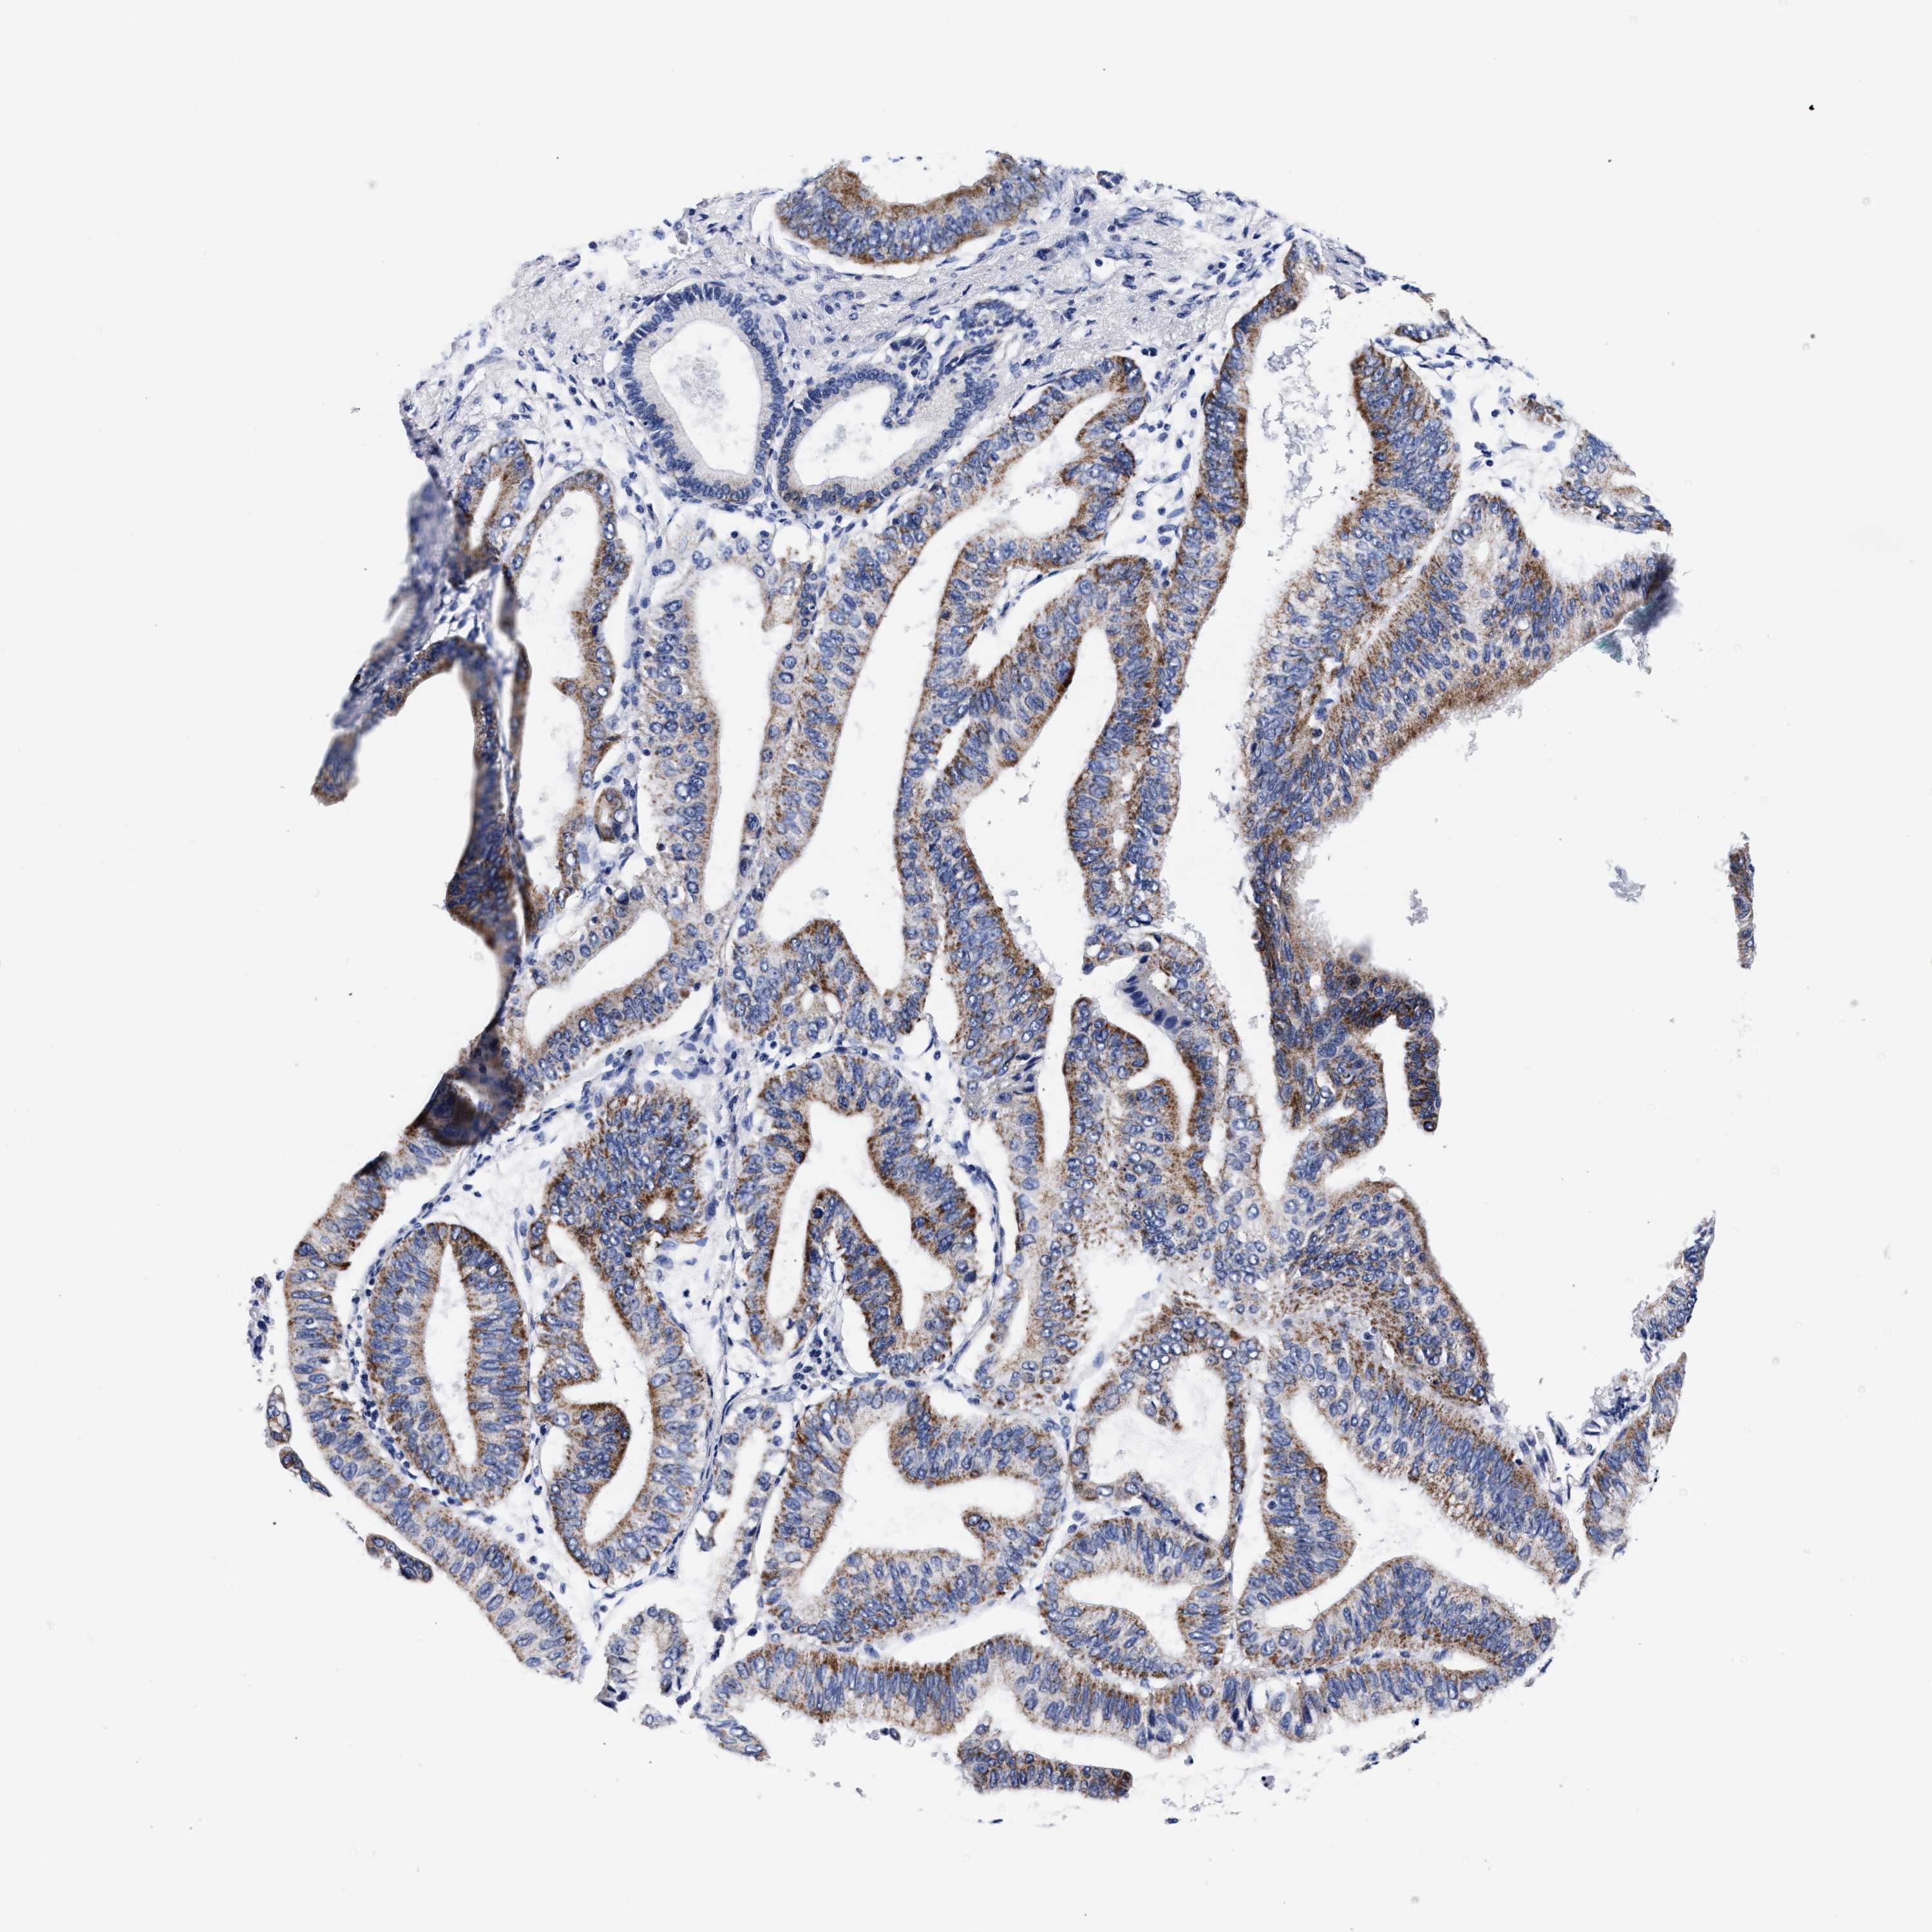

PANCREATIC CANCER - Protein expressioni

A mouse-over function shows sample information and annotation data. Click on an image to view it in a full screen mode. Samples can be filtered based on level of antibody staining by selecting one or several of the following categories: high, medium, low and not detected. The assay and annotation is described here.

Note that samples used for immunohistochemistry by the Human Protein Atlas do not correspond to samples in the TCGA dataset.

Antibody stainingi

Antibody staining in the annotated cell types in the current human tissue is reported as not detected, low, medium, or high, based on conventional immunohistochemistry profiling in selected tissues. This score is based on the combination of the staining intensity and fraction of stained cells.

Each image is clickable and will lead to virtual microscopy that enables deeper exploration of all samples and also displays staining intensity scores, fraction scores and subcellular localization as well as patient and tissue information for each sample.

Antibody HPA003159

Antibody CAB023293

Staining

High

Medium

Low

Not detected

Intensity

Strong

Moderate

Weak

Negative

Quantity

>75%

75%-25%

<25%

None

Location

Nuclear

Cytoplasmic/membranous

Cytoplasmic/membranous,nuclear

Adenocarcinoma, NOS

Adenocarcinoma, metastatic, NOS